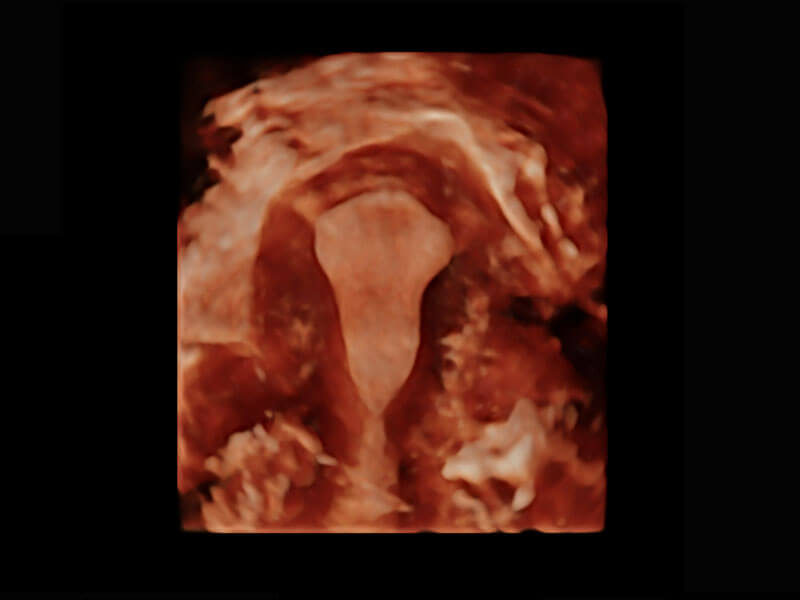

腔内三维-宫内节育器

P60优异的图像质量搭载专科探头,在妇科基础疾病的诊断、卵泡生长的监测、输卵管通畅情况的判别等方面为您提供生殖应用方案。